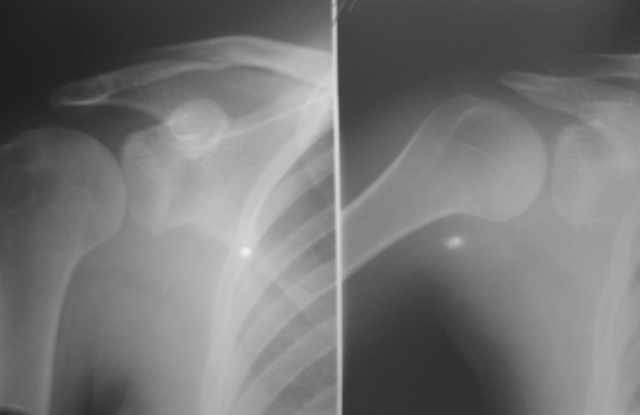

Пациентка 18 лет страдает привычным задним вывихом плеча

Выполнены операции: Задний артрориз с использованием аутотрансплантата, рцидив выввиха через 6 мес после операции (клинически и рентгенологически трансплантат рассосался). Остеотомия суставного отростка лопатки с увеличением угла антеверсии, рецидив через 9 мес. Какие варианты стабилизации возможны в данном случае? На рентгенограмме справа плечо в положении вывиха.